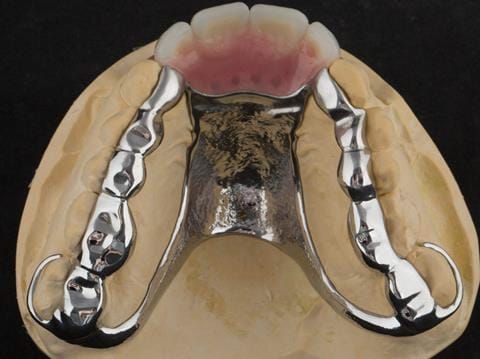

- Extract the upper 2-2 teeth and replace with an interim acrylic based partial denture. Reline the interim denture over 9 - 12 months, replacing with a definitive cobalt chromium based partial denture. The definitive denture would ideally be designed as an occlusal protective splint to reduce the the potential for mechanical wear and breakages of the moderately/heavily restored maxillary dentition. In addition, should further upper teeth require extraction they could be added on to the denture cobalt chromium framework - therefore a new prosthesis would not be required as future teeth are lost. This option would produce an excellent aesthetic outcome. This is the option the patient chose to have.

Following consultation and second discussion appointment the patient chose to have option 3 namely, a maxillary cobalt chromium based partial denture/protective occlusal splint. The clinical situation and treatment process is shown in detail below with photographs. The patient was successfully rehabilitated with this and her quality of life considerably improved. The clinical work was provided by Finlay and the technical work by Rowan.